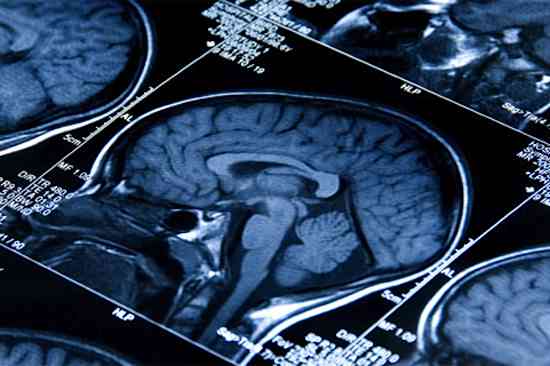

After her brain cancer became resistant to chemotherapy and then to targeted treatments, 26-year-old Lisa Rosendahl’s doctors gave her only a few months to live.

By adding anti-malaria drug chloroquine to her treatment, the combination stopped an essential process that Rosendahl’s cancer cells had been using to resist therapy, re-sensitizing her cancer to the targeted treatment that had previously stopped working. Along with Rosendahl, two other brain cancer patients were treated with the combination and both showed similar, dramatic improvement.

“Lisa is a young adult with a very strong will to live. But it was a high-risk, aggressive glioblastoma and by the time we started this work, she had already tried everything. For that population, survival rates are dismal. Miraculously, she had a response to this combination. Four weeks later, she could stand and had improved use of her arms, legs and hands,” says paper first author Jean Mulcahy-Levy, investigator at the University of Colorado Cancer Center.